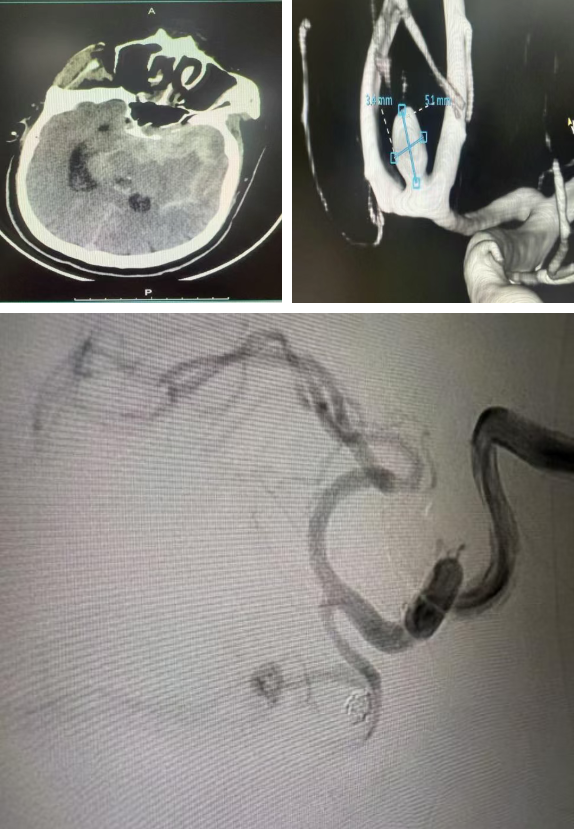

病情进展超出预期——就诊途中患者意识迅速恶化至昏迷。医院立即启动急诊绿色通道,急诊科医护团队第一时间为其实施气管插管、呼吸机辅助呼吸,同时紧急安排头颈部及主动脉CT血管造影(CTA)检查。检查结果让所有医护人员神经紧绷:患者同时罹患颅内前交通动脉瘤破裂与Stanford B型主动脉夹层,两种疾病单独发生时致死率已极高,叠加出现在临床上极为罕见。

完善术前准备后,神经外科曾实主任医师、张伟医师率先登台,全脑血管造影术精准定位动脉瘤形态与位置。在麻醉团队全程维持血流动力学平稳的护航下,手术医师将数枚超软弹簧圈精准送入动脉瘤腔内,直至实现完全致密栓塞。术后造影显示,动脉瘤彻底“消失”,载瘤动脉及分支血流通畅,第一阶段攻坚告捷。

▲神经外科手术造影显示载瘤动脉及分支血流通畅

短暂的术后稳定期内,麻醉监护团队将患者血压精准控制在安全区间,为下一阶段手术筑牢基础。随后,甲状腺乳腺血管外科文飞主任医师、段成主治医师接力开展“胸主动脉覆膜支架腔内隔绝术”。术中,医护团队精准操控输送系统,将覆膜支架成功释放于降主动脉夹层破口处,完美覆盖原发撕裂口。术后造影证实,破口封堵满意,假腔血流显著减少,真腔及重要分支血管血供完好,第二阶段手术同样圆满成功。